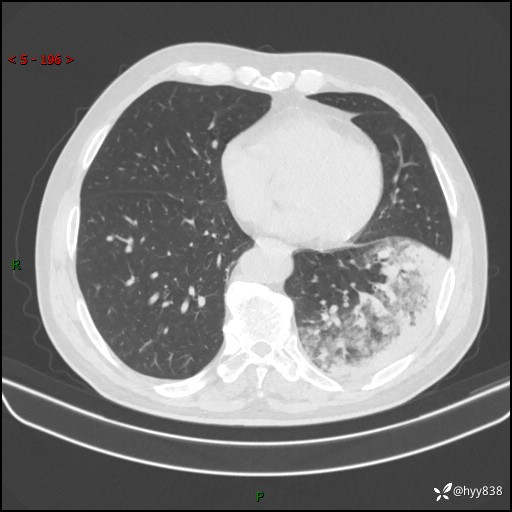

59岁/男,发热伴咳嗽3天。白班偶遇,“大叶性肺炎”,病原体挑战---结果公布~

【患者信息】:59岁/男

【主诉】:发热伴咳嗽3天

【检查】:胸部CT平扫